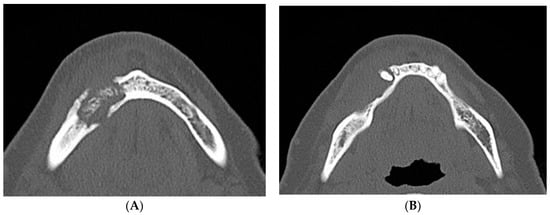

2. Case Report